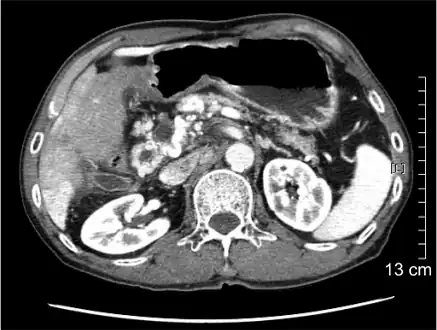

| Portal vein thrombosis seen with computed tomography. | |

Computed tomography scan showing portal vein thrombosis (with cavernous change of portal vein ) -

Portal vein thrombosis on computed tomography (left) and cavernous transformation of the portal vein after 1 year

The diagnosis of portal vein thrombosis is usually made with imaging confirming a clot in the portal vein; ultrasound is the least invasive method and the addition of Doppler technique shows a filling defect in blood flow. PVT may be classified as either occlusive or nonocclusive based on evidence of blood flow around the clot.[5] An alternative characterization based on site can be made: Type 1 is limited to the main portal vein, Type 2 involves only a portal vein branch (2a, or 2b if both branches are affected), and Type 3 if clot is found throughout both areas.[8] Determination of condition severity may be derived via computed tomography (CT) with contrast, magnetic resonance imaging (MRI), or MR angiography (MRA). Those with chronic PVT may undergo upper endoscopy (esophagogastroduodenoscopy, EGD) to evaluate the presence of concurrent dilated veins (varices) in the stomach or esophagus.[3] Other than perhaps slightly elevated transaminases, laboratory tests to evaluate liver function are typically normal.[1] D-dimer levels in the blood may be elevated as a result of fibrin breakdown.